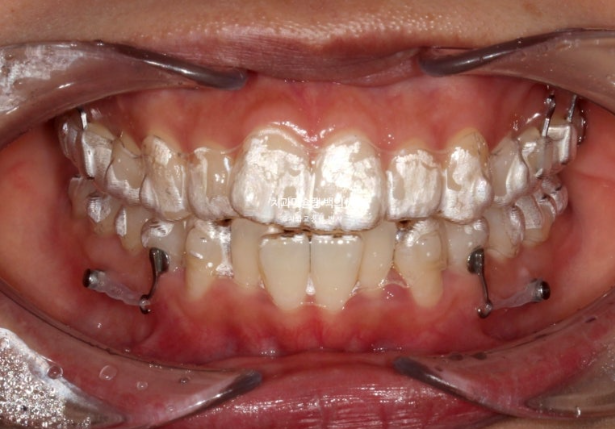

23.10

23년 10월 교정을 위해 온 30대 환자분입니다.

앞니는 뻗쳐있고 좌측 큰어금니 자리가 비어있습니다.

아래 앞니는 삐뚤하여 배열할 공간이 필요하고

위 첫번째 큰어금니 (제1대추치)가 한쪽은 발치되어있고 한쪽은 아직 발치는 안 했지만 발치진단이 나온 상황입니다.